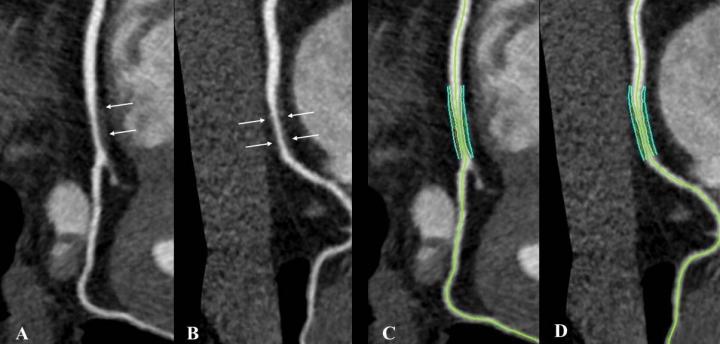

image: Noncalcified coronary plaque in an asymptomatic 52-year-old man living with HIV with a 10-year Framingham risk of 5%. Images show 256-section contrast-enhanced coronary CT angiography with electrocardiographic gating and curve reformat. A, B, CT scan shows a smooth noncalcified plaque in the right coronary artery (arrows) with 70%-80% stenosis. C, D, The right coronary artery plaque volume was 130 mm3 (cyan lines).

However, noncalcified plaque prevalence and volume were two to three times higher at coronary CT angiography in people living with HIV compared with non-HIV healthy volunteers after adjustment for cardiovascular risk factors. Noncalcified plaque may be more prone to rupture than calcified plaque.